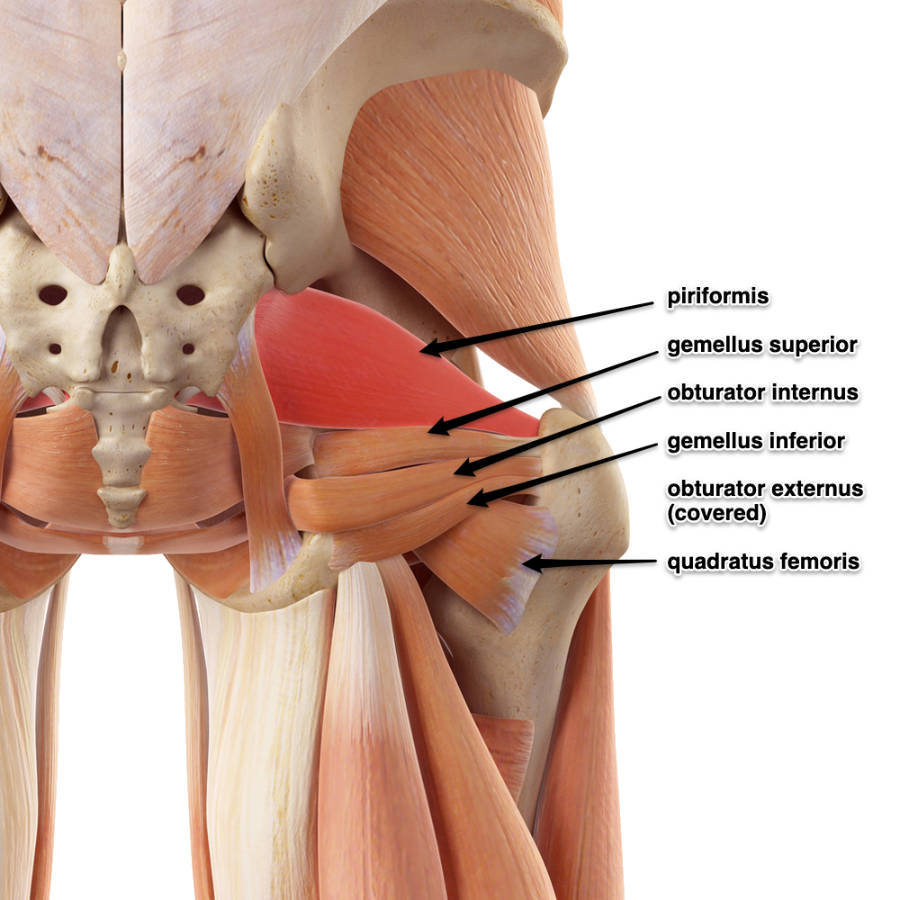

Анатомия мышц: Пириформис